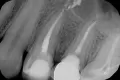

В середине ноября у меня разболелся зуб - верхняя правая 5-ка. Боль тупая, ноющая, иногда с ощущением распирания. Поставили диагноз пульпит, удалили нерв. Но после лечения оставалась легкая боль при накусывании, в январе зуб начал также реагировать на перкуссию. Я посетила консультацию у другого врача, сделала рентген. Мне сказали, что зуб запломбирован нормально, это может быть просто реакция организма на переохлаждение. Со времени той консультации прошел месяц, боль не ушла, зуб стал реагировать на горячее ощущением распирания. Еще иногда я замечаю неприятный привкус, идущий из пространства между этой 5-кой и 6-ой, как будто там что-то гниет.

На мой взгляд, зуб пролечен хорошо, но для полной картины и оценки необходим К/Т (трехмерный снимок). Все симптомы говорят о периодонтите.